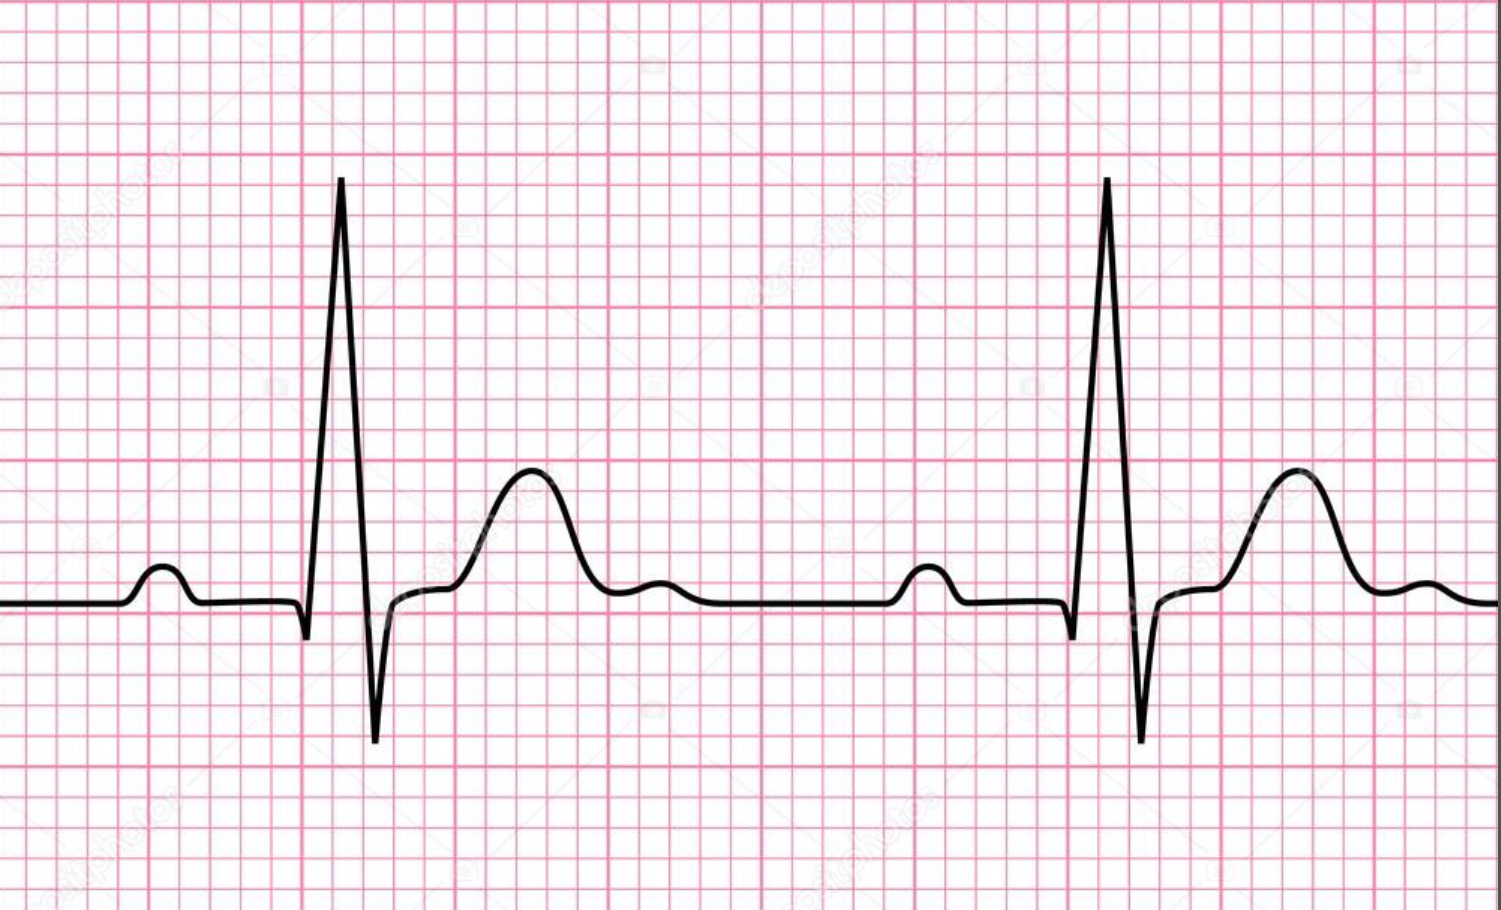

P wave

atrial depolarization

Precedes atrial contraction

QRS complex

ventricular depolarization

Precedes ventricular contraction

T wave

ventricular repolarization

PR interval

Name #1

QRS interval

Name #2

QT interval

Name #3

TP interval

Name #4